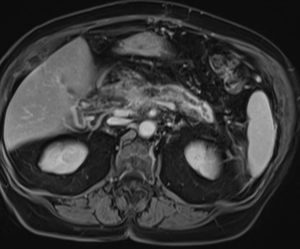

МР-диагностика образований поджелудочной железы